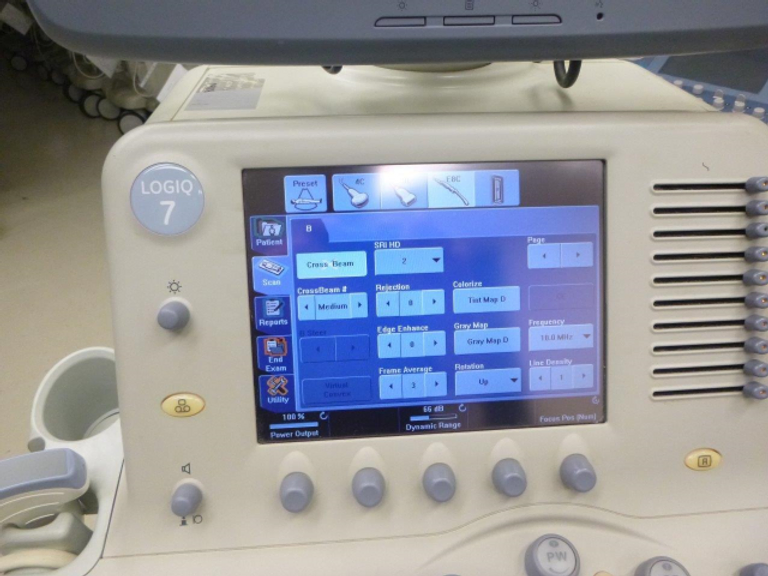

- User-Friendly Design: Designed with user comfort and efficiency in mind, the Logiq 7 features a intuitive touch-screen interface and ergonomic construction, ensuring ease of use for clinicians during diagnostic procedures.

- Tailored for Every Need: The Logiq 7 is compatible with an extensive range of ultrasound probes and transducers, including phased array, convex array, linear array, endocavity, intraoperative, and volume transducers, ensuring optimal performance across various imaging scenarios.